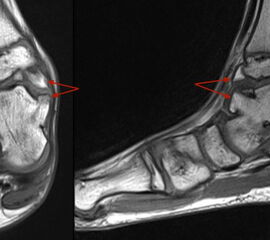

Stellvertretend für gutartige tumoröse Weichteilgeschwulste soll hier die pigmentierte villo-noduläre Synovialitis (PVNS) als wohl häufigste gutartige Weichteilneoplasie des Fußes erörtert werden. Die PVNS nimmt als einzige Entität in allen größeren Studien zu Fußtumoren einen der drei vorderen Plätze ein. Als Synonym der extra-artikulären Form der PVNS ist der Begriff des teno-synovialen Riesenzelltumors gebräuchlich. Die sehnenscheiden- und gelenkkapselreiche Fußanatomie prädestiniert für die Entstehung einer PVNS (Abb. 32). Das weibliche Geschlecht ist doppelt so häufig betroffen, das bevorzugte Alter liegt zwischen 30-50 Jahren. Eine schmerzlose, nur langsam größenprogrediente Schwellung ist das häufigste Symptom. Die Rezidivrate wird mit bis zu 30% angegeben 49. Bei der PVNS handelt sich um einen fibro-histiozytären Tumor (echte Neoplasie) und nicht wie ehemals angenommen um ein inflammatorisches oder posttraumatische Geschehen. Für die intraartikuläre Form, die wiederum in eine noduläre/lokalisierte und diffuse Form unterteilt werden kann, stellt das Sprunggelenk die dritt-häufigste Lokalisation am gesamten Körper dar (Abb. 33).

Im Röntgen zeigt sich gelegentlich eine gut abgrenzbare Weichteilformation (bei nodulärer Form) und knöcherne Druckarrosionen der angrenzenden Knochen. Sekundäre arthrotische Veränderungen der angrenzenden Gelenke sind möglich. Die MRT kann mit einem stark T2-gewichtetem Gradientenecho sog. Suszeptibilitätsartefakte der Hemosiderin­ablagerungen darstellen. Diese führen gewöhnlich zu charakteristischen Signalaus­löschungen in T1 und T2 gewichteten Sequenzen. Eine Kontrastmittel-Aufnahme erfolgt in der Regel diffus und inhomogen. Die Therapie besteht in einer offenen Resektion. Wir raten dringend davon ab, intraartikuläre, lokalisierte Formen der PVNS per Arthroskopie resezieren zu wollen. Dieser Tumor sollte, wenn möglich, marginal und nicht intraläsional reseziert werden. Eine arthroskopische Zerkleinerung mit dem Shaver würde aus einer nodulären Form eine diffuse Form produzieren und die Rezidivwahrscheinlichkeit deutlich steigern. Ebenso ist vor einer Radiosynoviorthese (RSO) bei Vorliegen einer nodulären Variante abzuraten. Bei diesem nuklearmedizinischen Verfahren, welches gewöhnlich Anwendung bei chronisch entzündlichen Gelenkerkrankungen findet, werden Beta-Strahler in Gelenke injiziert. Ein therapeutischer Effekt hat sich bisher nicht nachweisen lassen.